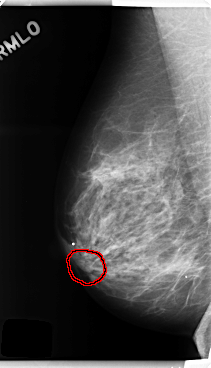

C_0252_1.RIGHT_MLO

RIGHT_MLO LINES 4776 PIXELS_PER_LINE 2736 BITS_PER_PIXEL 12 RESOLUTION 50 OVERLAY

FILE: C_0252_1.RIGHT_MLO.OVERLAY

TOTAL_ABNORMALITIES 1

ABNORMALITY 1

LESION_TYPE MASS SHAPE OVAL MARGINS CIRCUMSCRIBED

ASSESSMENT 4

SUBTLETY 3

PATHOLOGY BENIGN

TOTAL_OUTLINES 1

BOUNDARY